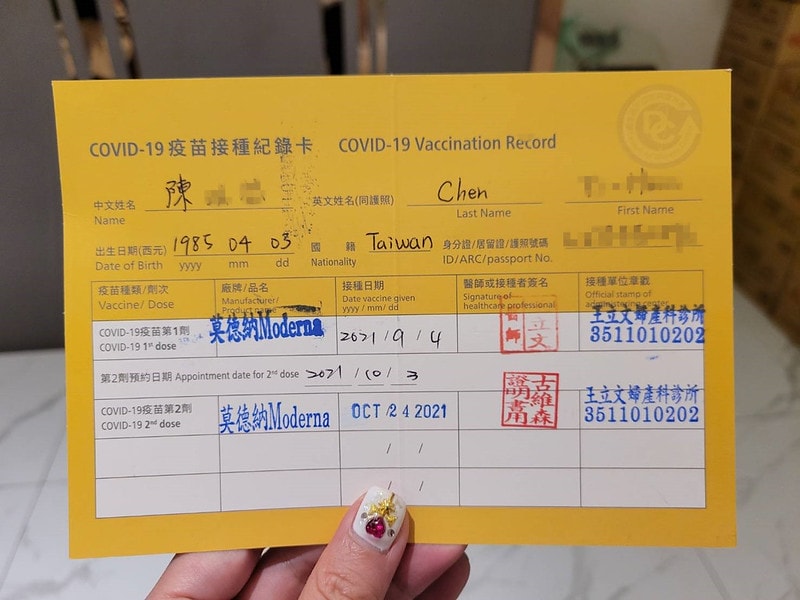

關於疫苗

其實我已經打完兩劑了

莫德納國外有做過實驗孕婦可以打

所以你們會發現只要是孕婦

基本上疫苗都是打莫德納喔

好處是孕婦真的是基本上不用排隊

下次再寫一篇打疫苗的心得文好了